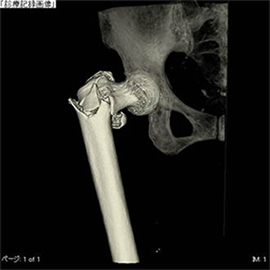

4. 金属アーチファクト抑制技術 (SEMAR)

手術で金属を埋め込まれている患者さんの金属アーチファクトの低減が可能となり、従来は評価しづらかった金属周囲が、より見やすく評価しやすくなりました。

CTの検査画像例